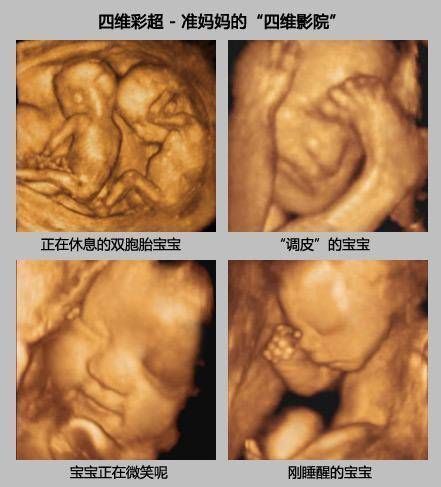

孕期产检,相信不少孕妈妈都很期待四维排畸这一项了,四维彩超排畸检查有不少准妈妈也想带着准爸爸进去,一同分享这其中的喜悦。

【为什么有些医院做四维彩超不让家属陪同这些原因,大家有权知道】小茹怀孕24周左右的时候,身边朋友提醒她这个时候需要做四维大排畸了,不仅能知道胎宝宝发育状况,还可以提前看到宝宝的长相。